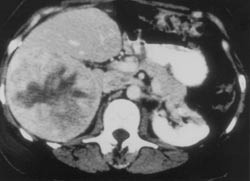

CT-abdomen viste en stor tumor, 12 – 13 cm i diameter i området for venstre binyre, mulig retroperitoneale lymfeknutemetastaser og to store metastaser med diameter 8 – 9 og 7 – 8 cm i henholdsvis høyre og venstre leverlapp (fig 1). Pasienten ble henvist til Radiumhospitalet som vurderte pasienten som inoperabel på grunn av store levermetastaser. Økende abdominalsmerter og vanskeliggjort matinntak gjorde at pasienten ble henvist til Rikshospitalet med tanke på palliativ kirurgi. Pasienten ble laparotomert, og man kunne påvise en stor binyretumor med flotterende tumormasser ned i nyrevenen og ut i v. cava. Tumormassene i venesystemet ble melket opp i en monstrøst forstørret binyrevene og hele tumor ble fjernet, dog med noe usikker radikalitet oppad og medialt. Ved operasjonen fant man levermetastaser forenlig med CT-funnet. Metastasen i venstre lapp (segment II og III) var velavgrenset og lå som et lodd over ventrikkelen. Denne ble resecert. Metastasen i høyre leverlapp affiserte alle segmentene (V, VI, VII og VIII), og man fant det uforsvarlig samtidig å resecere høyre leverlapp på grunn av lite gjenværende levervev (segment I og IV). Postoperativt kom pasienten seg bemerkelsesverdig fort, og hennes allmenntilstand bedret seg radikalt i forhold til tilstanden preoperativt. Hun ble overflyttet til sentralsykehuset tredje postoperative dag og ble utskrevet til hjemmet en uke senere. Det ble avtalt CT-kontroll tre måneder etter primæroperasjonen med tanke på eventuell reseksjon av den gjenværende levermetastasen. Postoperativt fikk hun et spontant fall i urin-kortisolutskilling per døgn fra 3 191 nmol/ 24 timer til 1 118 nmol/24 timer, og nivået av androgenmetabolitter (androstendion, DHEAS-sulfat og testosteron) ble halvert (tab 2).